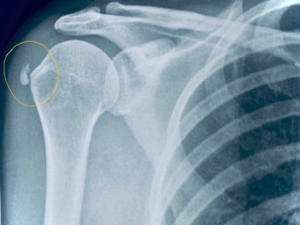

Η κλινική εικόνα σε συνδυασμό με την ακτινολογική θέτουν τη διάγνωση.

Εικόνα 1. Στην ακτινογραφία είναι εμφανείς οι επασβεστώσεις κοντά στο Μείζον Βραχιόνιο όγκωμα.